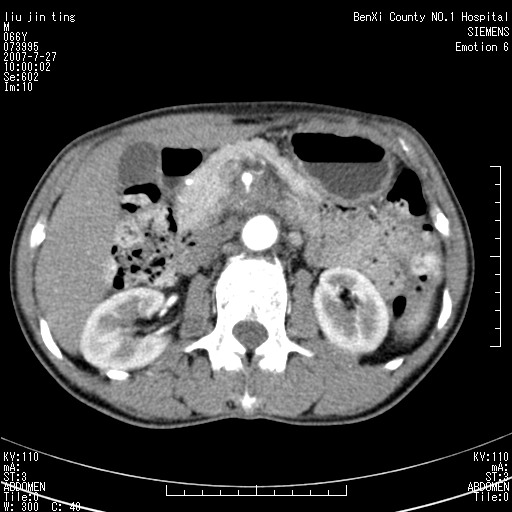

腹痛,背痛,无恶心呕吐,不黄,彩超示胰腺钩癌,ct扫描病灶平扫30-40hu,增强后动脉期40--60hu,静脉期50-68hu,真的是钩突上的么?您要试一试么?

动脉期

静脉期

沿着肠系膜上动脉呈匍匐性生长的软组织肿块,形态不规则,包绕肠系膜上动脉,呈明显强化,考虑来源于肠系膜的恶性肿瘤

沿着肠系膜上动脉呈匍匐性生长的软组织肿块,形态不规则,包绕肠系膜上动脉,呈轻-中度强化,考虑来源于肠系膜的恶性肿瘤。